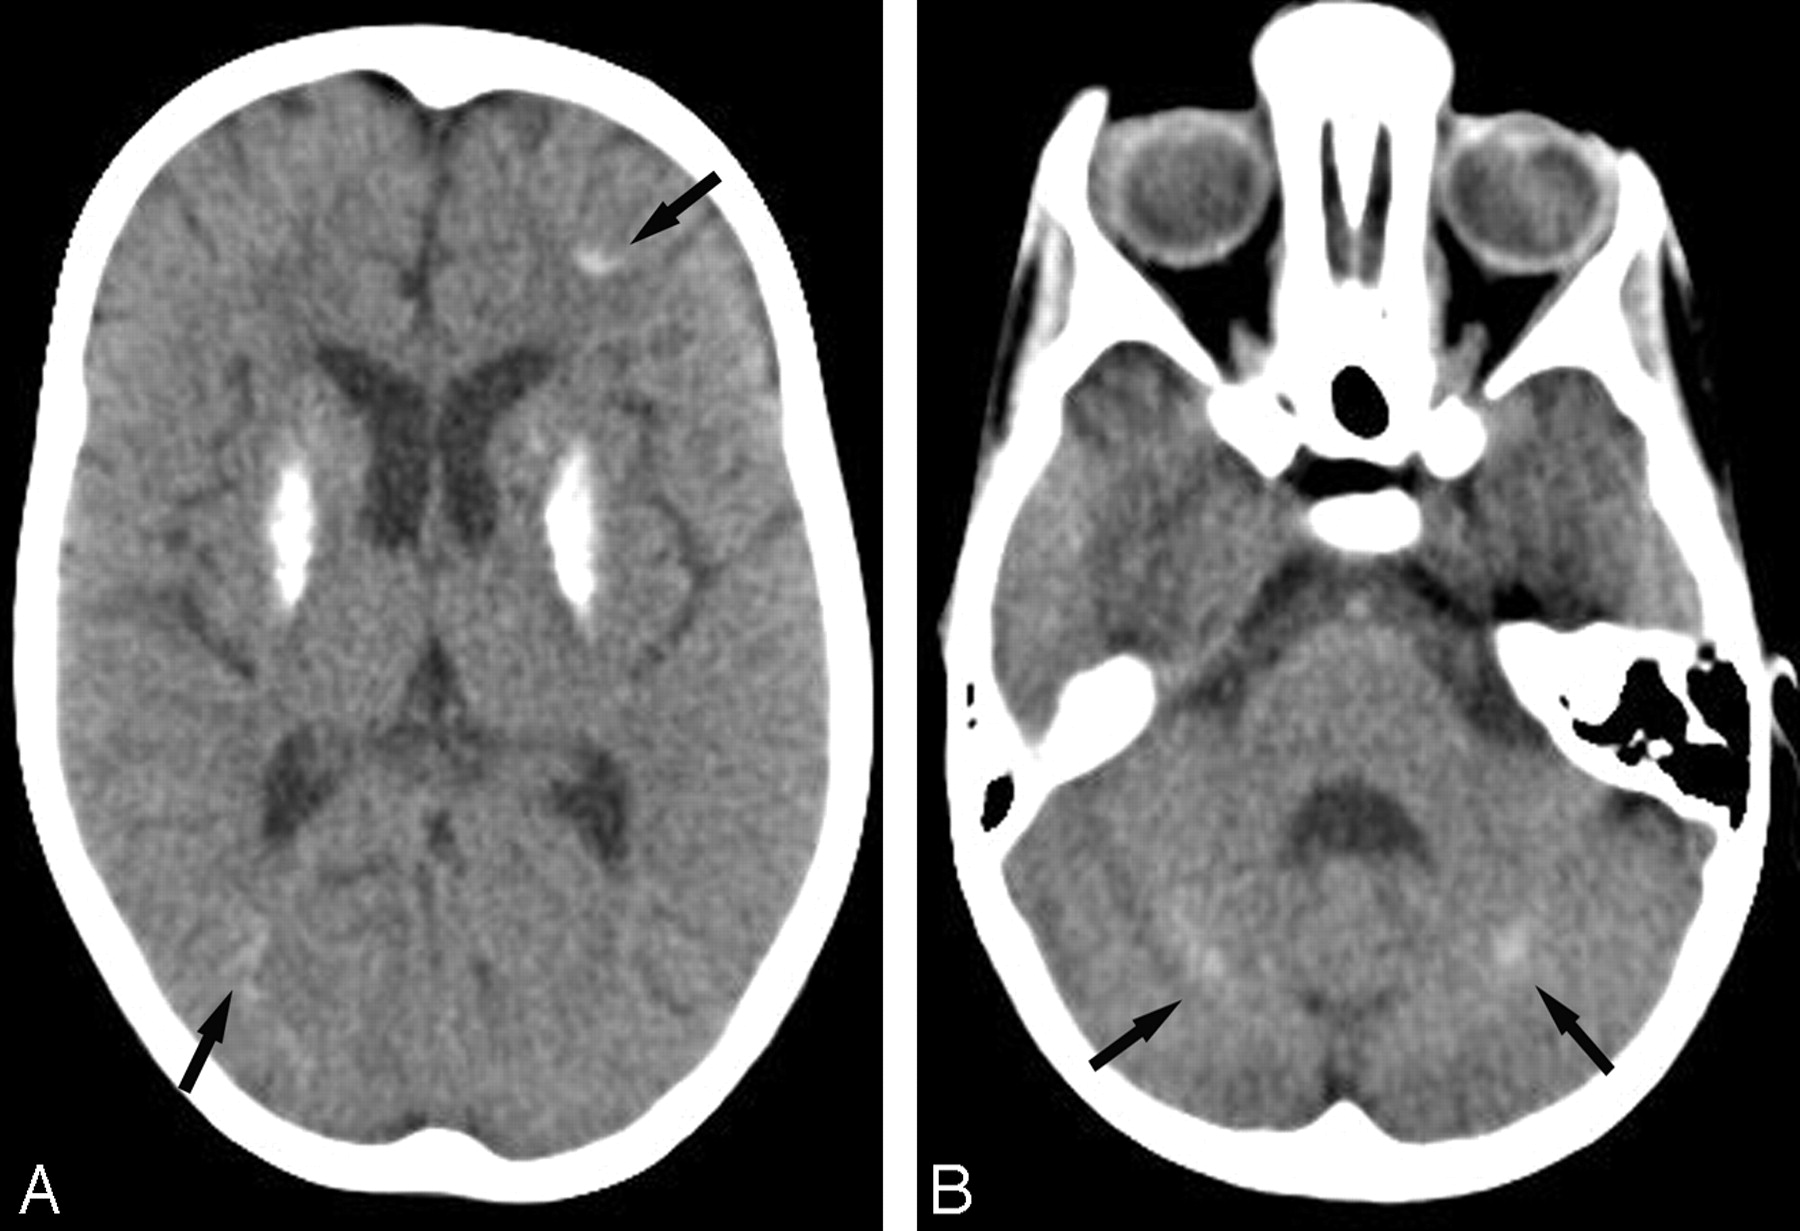

Patient 6 at 6 years of age (CS I). A, Axial CT scan at the basal ganglia level shows severe bilateral calcifications in the putamen. Subtle calcifications are seen in the frontal and parietal cortex at the depths of the sulci (arrows). B, Axial CT scan of the posterior fossa shows bilateral slight calcifications in the dentate nuclei (arrows).

Brain calcifications were present in 16 of 18 patients. Calcifications were only absent in patients 12 and 18 (type II and COFS) at 4 months and 2 years of age, respectively. In patient 19 (COFS), calcifications were absent at 9 months but present at 2 years. Regarding the entire cohort, brain calcifications could be detected from 1 year of age (patients 5 and 13) and were observed in all patients older than 3 years of age (CS type I and III). Calcifications were typically bilateral and symmetric, ranging from punctuate to severe, and were most frequently seen in the putamen (15/18). Putaminal calcifications were either isolated (5/15) or associated with calcifications in the cortex, the dentate nuclei, the caudate nuclei, the pallidum, and, more rarely, the white matter or the thalami (Fig 1). Cortical calcifications were larger at the depths of the sulci in the occipital, parietal, and frontal lobes. In the frontal lobes, they extended to the white matter in 2 patients (patient 5, type I, and patient 13, type II). Patient 17 (type II) had vermian calcifications associated with calcifications of the dentate nuclei. Patient 6 (type III, 28 years of age) had tentorial calcifications.

Overall, there was no strict correlation between the extent or severity of the calcifications and the age of the patients, the severity of their neurologic symptoms, or the degree of cerebral atrophy. Nevertheless, the largest calcifications were seen in the oldest patient of our series (patient 3, type III, CT scan at 44 years of age) in the dentate nuclei, the putamen, and the caudate nuclei. Additionally, a particular pattern of brain calcifications was seen in 4 of the most severely affected patients (3 patients with CS II and 1 with COFS). These patients (13, 14, 17, and 19) had almost identical distribution of calcification, including bilateral involvement of the lenticular nuclei and major and bilateral calcifications in the cortex in the depths of the sulci and in the nearby leptomeningeal vessels in the frontal and parieto-occipital subarachnoid spaces (Fig 2).

Brain calcifications were seen in infants as young as 1 year of age in our cohort and from 6 months of age in a previous report.18 They are usually observed within months or years after the onset of the neurologic symptoms. Conversely, this means that calcifications can be missing at early stages, especially in patients presenting the most severe forms of CS. Calcifications are noted in most patients with CS older than 3 years of age. There is no clear correlation between the presence of calcifications and specific neurologic symptoms, but 2 different patterns of calcifications can be recognized in different clinical subtypes. In patients with classic CS, symmetric, attenuated, and homogeneous putaminal calcifications are usually predominant but can sometimes appear punctuate and slightly asymmetric.11 In patients with severe CS II and COFS, diffuse cortical calcifications at the depths of the sulci are associated with the putaminal calcifications. This particular cortical topography has been reported previously in a neuropathologic study, along with calcifications of neighboring arteries.19 Calcified leptomeningeal vessels, also described in other CS neuropathologic reports,1,9,20 were present in 5 of our patients with CS II and COFS.